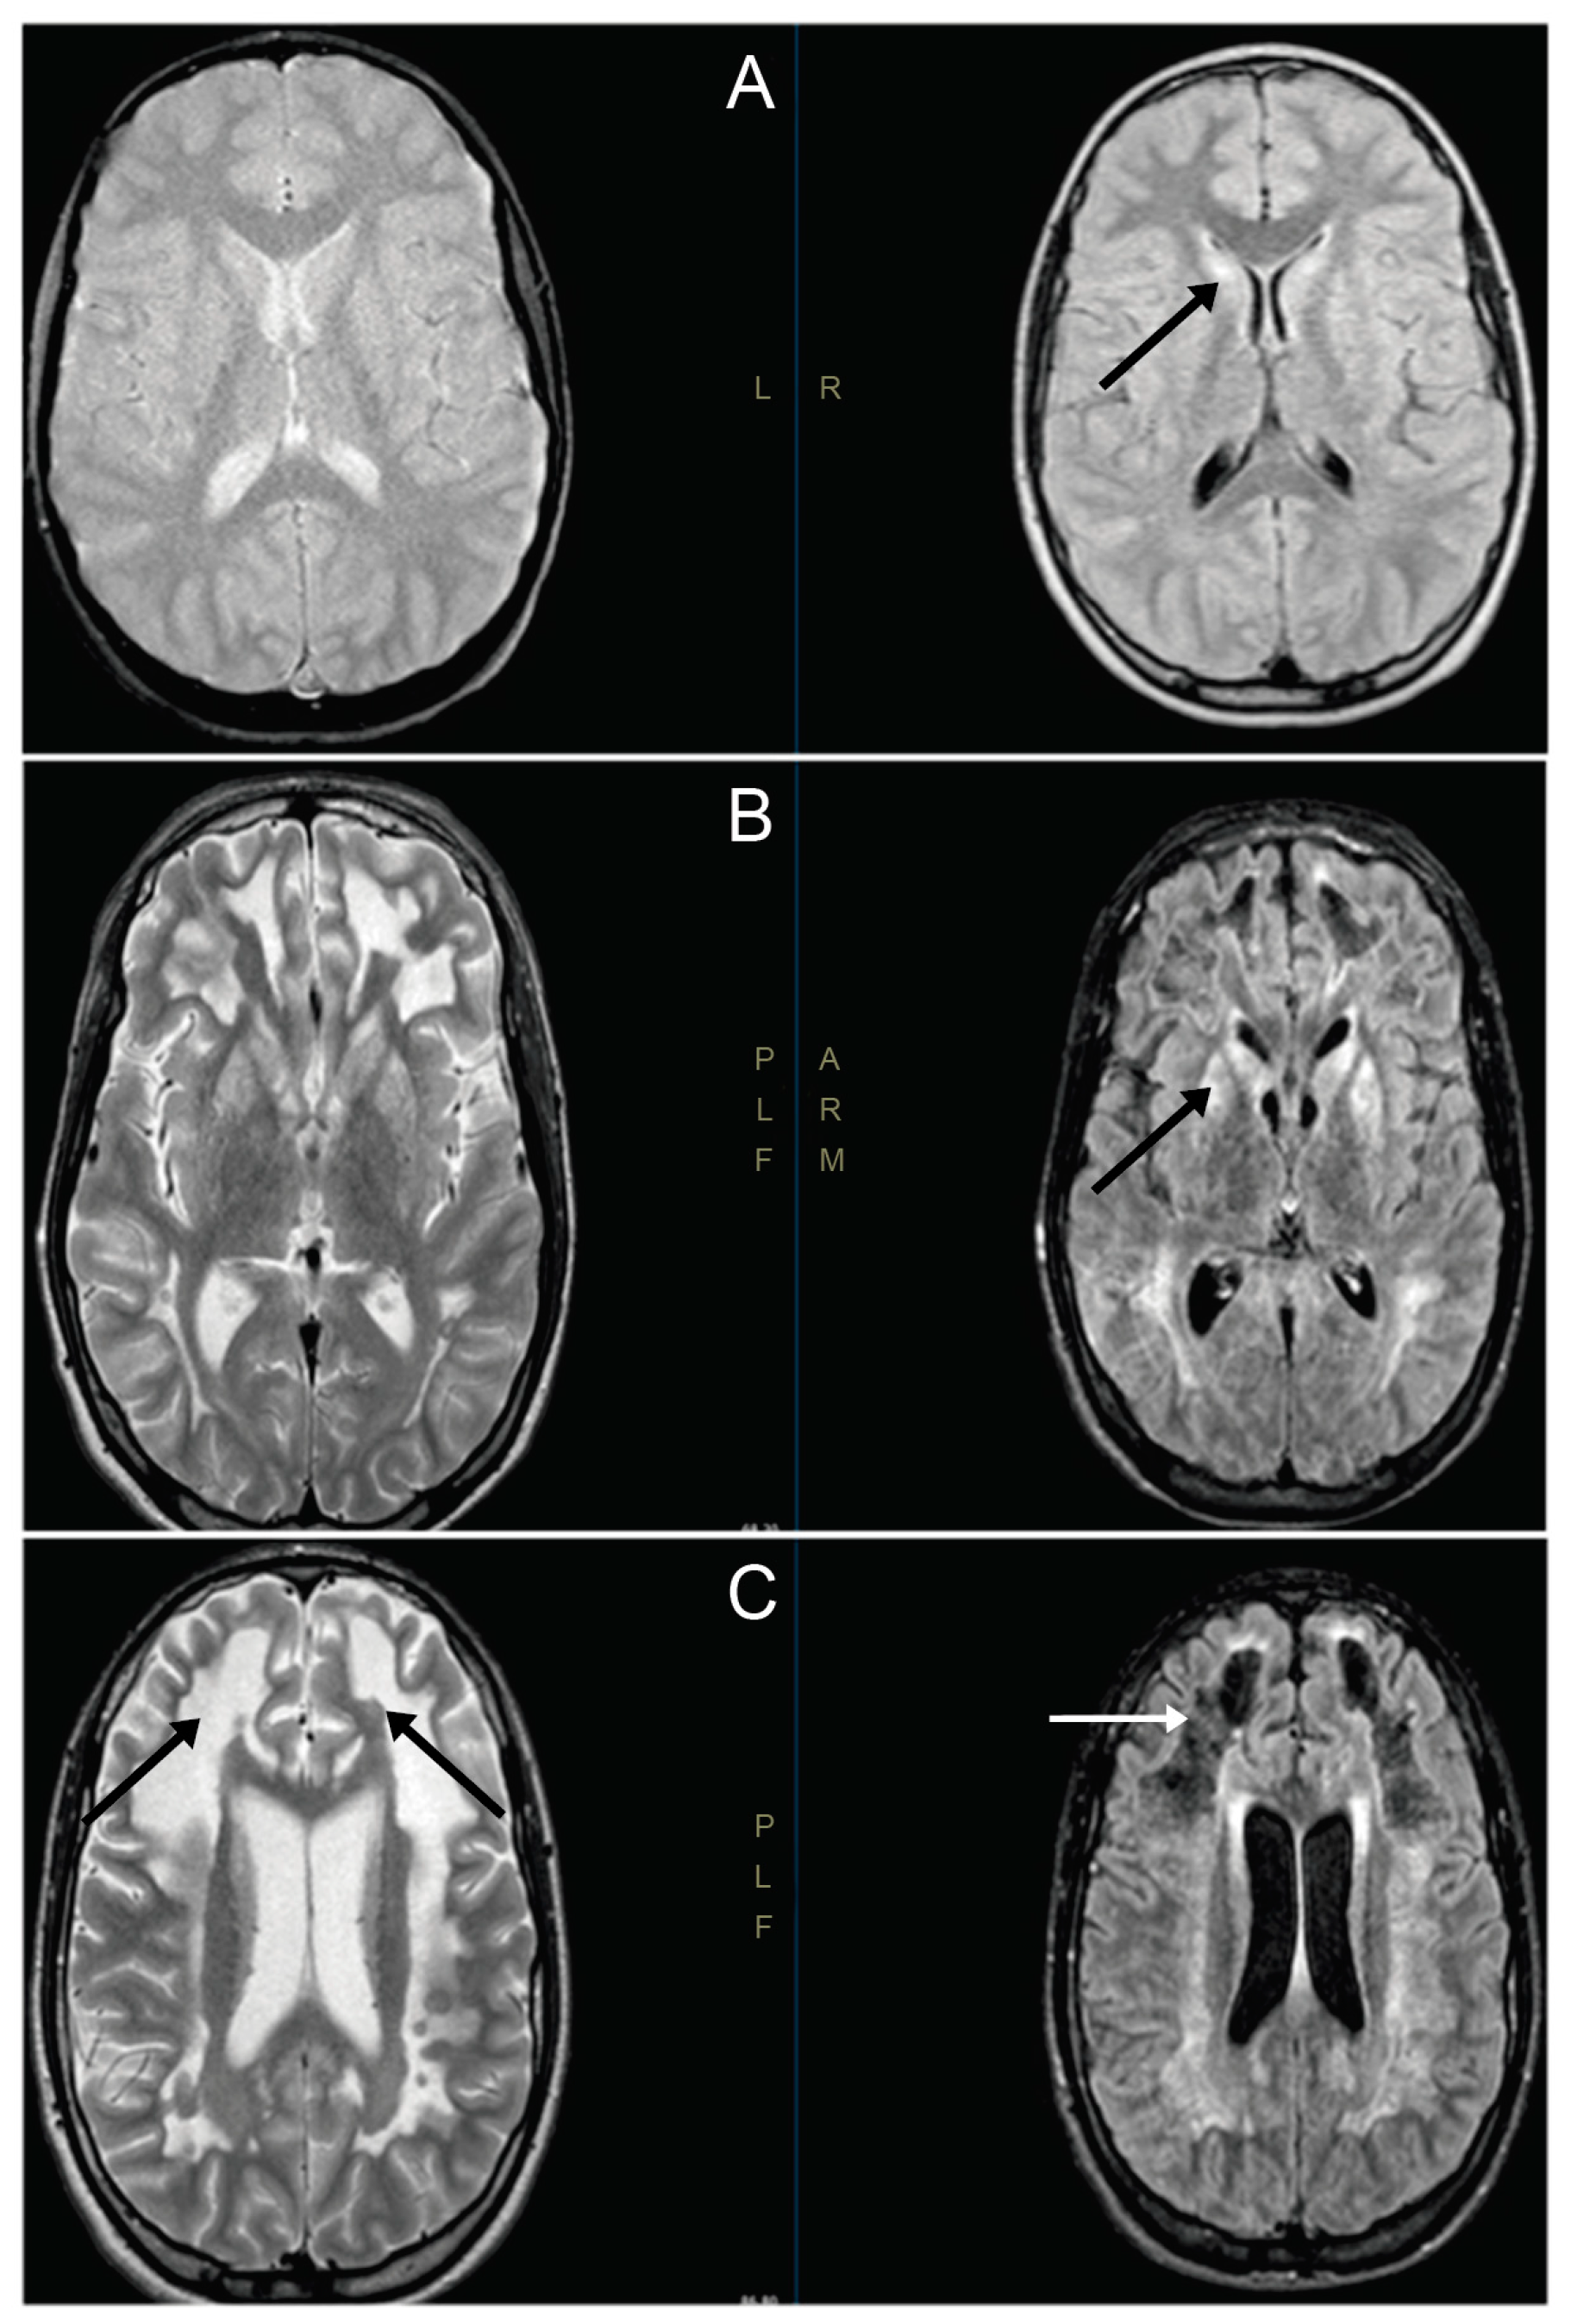

3.1. Clinical Cases